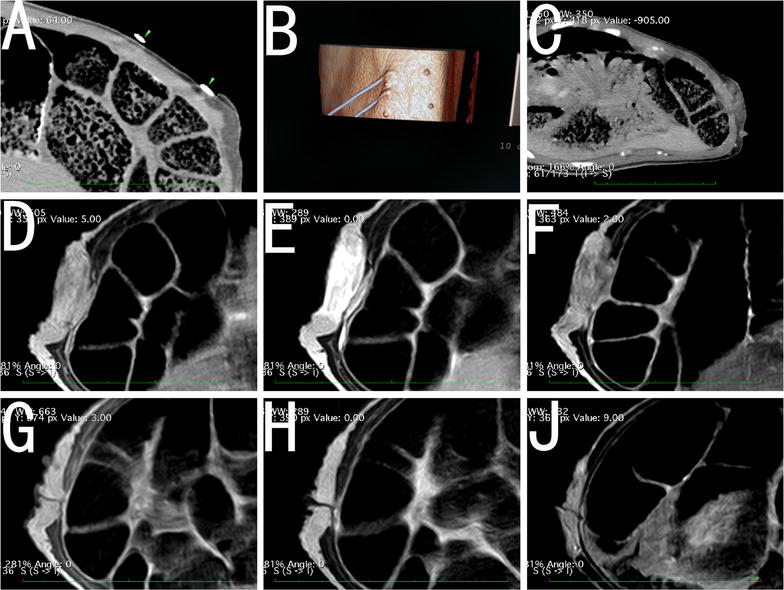

摘要:目的探讨不可逆电穿孔(IRE)对乳腺组织和乳腺癌动物模型的安全性、可行性和皮肤效应。方法:在这项研究中使用了八头猪。用不同皮肤-电极距离的猪的左乳房进行不可逆电穿孔,右乳房作对照。电极被放置在离皮肤1 - 8毫米的地方,电极间距为1.5 - 2厘米。在特定时间点进行影像学和病理学检查评估。密切观察动物生命体征、皮肤损伤、乳腺组织变化和消融疗效。8只有VX2乳腺癌植入或没有的模型兔用以进一步评估乳腺癌治疗后薄皮的损伤和修复。超声造影与超声弹性成像观察消融的疗效和安全性。结果:在不可逆电穿孔过程中,猪乳房皮肤的颜色发生了可逆的变化。皮肤-电极距离为3毫米时,乳房皮肤颜色明显改变,在中心区域变成白色,周围区域为紫色。不可逆电穿孔几天后,检测出小的化脓性皮肤损伤。当皮肤-电极距离为5 - 8毫米时,乳房皮肤在不可逆电穿孔过程时变红。然而,用大体病理学和苏木精-伊红染色评估发现皮肤结构是正常的。当皮肤-电极间距为1 mm,兔乳房皮肤出现萎缩。当皮肤-电极间距为≥5 mm,无论有无乳腺癌细胞植入的家兔模型均无皮肤损伤。不可逆电穿孔后,已确定靶乳腺组织或癌完全消融,靶组织和最外层表皮细胞均有凋亡。在幸存的动物乳房中,发现正常皮肤和完整毛发的乳房再生。此外,超声或HE染色均未发现大面积纤维化或肿块形成。结论:在不可逆电穿孔过程中,当皮肤-电极距离≥5毫米时皮肤结构保存完好。乳腺再生无肿块形成或明显纤维化。关键词:不可逆电穿孔 乳腺 成像 病理 细胞凋亡 皮肤背景:近年来,乳腺癌保乳治疗的使用已得到临床证据的支持,影像引导下的消融技术,如射频消融、高强度聚焦超声,已成为乳腺肿瘤的治疗有用的方式。在乳腺癌切除术中,如果病灶太大或表面较浅,乳房皮肤可能受损,不完全消融可能发生以防止损伤。此外,许多亚洲妇女乳房体积相对较小,因此在这一人群中,热消融时皮肤损伤的风险增加。放疗后保乳纤维化(即乳腺和皮肤纤维化)是放疗后常见的晚期毒性。约45%的患者经历了辐射引起的纤维化相关疼痛,在切除有放射性纤维化的组织后可能发生更严重的纤维化。这是影响乳腺癌放疗后生存质量和美容效果的主要因素。乳腺癌切除后,如果皮肤没有受损,正常乳腺组织再生,无肿块形成或残留肿瘤,则上述问题将得到解决。不可逆电穿孔技术的应用使这一目标成为可能,因为在烧伤后皮肤细胞凋亡可能是有选择性的。但是还没有在大的动物模型中研究使用乳腺癌根治术的报告。以前的研究主要报道了IRE的疗效,但我们集中在皮肤损伤,纤维斑块的形成和消融后乳房的重吸收。在这项研究中,我们对两种动物乳腺癌模型用接近皮肤表面的电极(1 - 8毫米)进行了治疗。评估了它的安全性和可行性,特别是它对皮肤的潜在损伤及导致乳房纤维化的形成。方法:用五指山猪进行正常乳房的射频消融实验研究。用新西兰大白兔进行乳腺癌和乳腺癌的射频消融研究。猪的胸部比较大,皮肤厚,便于在进行皮肤手术时准确测定电极与皮肤的距离。局部乳腺癌的皮肤可能不同于典型的健康皮肤,皮肤变薄可能是由于营养不良、皮肤侵犯和局部肿瘤张力引起的。因此,不可逆电穿孔热损伤皮肤的风险会增加。由于兔皮肤薄,我们用新西兰大白兔研究皮肤损伤。建立了兔VX2肿瘤模型,以检验乳腺癌根治术的安全性。在不可逆电穿孔治疗前和治疗后,通过大体病理和组织病理学对所有乳腺动物的乳房、乳头、肌肉、乳腺导管和乳腺、乳房肿块形成、消融区纤维化和乳房再生进行了评估。不可逆电穿孔:所有的动物在手术前禁食12小时。备皮,消毒和覆盖洞巾。手术开始前肌注舒泰(4.4 mg/kg),静脉注射3%戊巴比妥钠(1ml/ kg)维持全身麻醉。所有的动物在术前皮下注射0.01毫克/公斤丁丙诺啡镇痛,然后每12小时一次连续72小时。在IRE过程中,每只动物接受琥珀酰胆碱(2 mg/kg)。在IRE前10min,静脉注射泮库溴铵(0.15 mg/kg)减少肌肉收缩。计算机断层扫描(CT)和超声引导下,确定皮肤和电极之间的精确间距。一位经验丰富的技术专家进行CT和磁共振成像(MRI)扫描。采用实时超声监测技术将乳腺电极植入乳房的正常位置。研究组有超过5年的介入放射学经验。乳头位于两个电极之间,在研究中大部分乳房位于消融区。平行电极和合适的位置也被CT扫描所证实。肌肉完全放松后,我们开始使用心电图(ECG)同步模式进行射频消融。IRE后,回顾了电压和电流图以及超声造影和CT图像来评估消融效果。如果没有完成靶区的完全消融,则重复治疗。猪乳房的IRE消融:健康成年五指山猪8头,体重16~18公斤,分为IRE组(6头猪)和假处理组(2头猪)。三只猪的左乳房被消融或加工。右乳房被用作对照,任何猪的都不接受治疗。假手术组在不做消融的情况下,将电极插入左乳房。在IRE组,进行左侧乳房的IRE消融。在IRE组,一头猪有三个乳房,电极和皮肤之间的距离为3毫米,剩下的五只猪电极和皮肤之间的距离为5到8毫米。电极和皮肤之间的距离被定义为电极与皮肤表面暴露部分之间的最短距离。假手术组在不做消融的同时,将电极插入乳房的预定位置。围手术期进行CT和MRI,做活检或切除乳房作病理检查。家兔乳房的IRE消融:为了确定是否会破坏薄皮肤,在新西兰大白兔身上放置了接近乳房皮肤(1或3毫米)的电极。电极保持平行于皮肤平面,四个消融区的距离为1毫米,另外四个消融区为3毫米。总共对四只兔子进行了八次IRE试验。IRE之后的1, 3, 7天和14天,检查肿块形成、纤维化和皮肤变化。乳腺癌模型的IRE: 将新鲜的VX2肿瘤分成1 - 2毫米直径的组织块,没有坏死或液化碎片。我们在四只兔子的乳房皮下植入一个新的肿瘤。每只兔子产生两个乳腺癌模型。皮肤-电极距离小于8毫米。1周后,所有8个乳腺肿瘤直径增加到1到1.5厘米,用超声评估肿瘤大小。在IRE开始前、开始后1天和7天用彩色多普勒超声、超声弹性成像及超声造影。我们于第3天切除了4只兔子的四个乳腺肿瘤,进行病理检查;在实验后期的时间点,没有超声波检查。剩下的4个乳腺肿瘤定期评估至少1个月。用超声造影评估是否完全消融,并应用超声弹性成像技术检测IRE后组织刚度的变化,作为评估完全消融的一个潜在的方法。弹性成像探头频率为4-15 MHz。选择合适的切片后,切换到实时剪切波弹性成像模型,并在消融区放置一个弹性成像取样框架。在3~5 s图像稳定后,将90%的图像采样帧填充为彩色,选择直径为3厘米的周期作为测量区域,得到平均弹性值。测量重复三次。尽量避免在表面皮肤留下超声波探头的痕迹。超声造影成像,静脉注射1.2毫升的sulfohexafluoride微泡后,我们开始约2分钟的影像。所使用的超声波频率为3 - 9兆赫。IRE之前和之后进行超声弹性成像及超声造影。HE染色与免疫组织化学:取乳房标本进行HE染色和细胞凋亡试验。IRE后立即及1、3和1周后用TUNEL和caspase-3对凋亡细胞进行检测。TUNEL阳性结果为棕黄色核染色。caspase-3蛋白阳性染色为胞浆棕黄色染色。评估了皮肤、乳腺血管、肌肉、乳腺、导管和基质中的凋亡细胞分布。结果:猪乳房的IRE消融:在皮肤-电极距离为3毫米IRE之后,猪胸部皮肤的颜色开始变为红色,然后变成白色,然后变成紫色,最后恢复到正常的颜色。术后2周,皮肤局部有少量化脓灶。痂形成,4周后,皮肤就恢复正常。其余两个乳房正常。当皮肤-电极距离约为5 - 8毫米时,乳房皮肤变红,消融区的中心区域变成白色,乳头周围有红色。皮肤-电极距离越近,术中皮肤颜色变化越明显和迅速。2小时后皮肤颜色恢复正常,穿刺点变红时可见少量液体。IRE之后,消融的乳房充血,肿胀,坚硬。在3个月内,大多数动物的乳房皮肤都是正常的,有完整的毛发和皮肤。在消融后3个月,消融区无纤维质形成。兔乳腺及乳腺癌的IRE消融: IRE之前,兔的乳房皮肤看起来正常。当皮肤-电极距离为1毫米时,皮肤在IRE后变红。术后第三天出现一个小的化脓性病变。一周后,皮肤表现出黄化、脱落。2周后,皮肤再生,无瘢痕形成。三周后,皮肤上只出现一个小痂,新毛发生长明显,消融区大部分皮肤恢复正常。IRE两个月后,皮肤和肌肉周围的乳腺组织正常。其他三个乳房,皮肤变得干燥和黄色,脱毛发生1周后。术后2周无化脓灶,但新皮肤生长,3周后毛发和皮肤均正常。当皮肤-电极距离为3毫米时,四个消融区的皮肤颜色瞬间变为红色,没有皮肤结构损伤或脱发,家兔乳房内无瘢痕或纤维化形成。建立兔乳腺VX2肿瘤模型后,通过病理评估和超声证实肿瘤的形成。植入后10天肿瘤直径逐渐增加1~2厘米,无液化或坏死。IRE后第一天,乳腺肿瘤变硬变大,第二天肿瘤开始变软萎缩,呈时间依赖性。当皮肤-电极距离为1毫米时,一个乳房的皮肤有脓毒症的迹象,并有疤痕愈合。当皮肤-电极距离约为3毫米时,覆盖肿瘤的乳房皮肤出现化脓,并且在消融区域没有发现血液供应。当皮肤-电极间的距离≥5毫米,没有皮肤溃烂化脓或脱毛的迹象。一个月后,所有的动物都有正常的乳房皮肤。HE染色:IRE之后,消融的乳房变得充血、肿胀和坚硬。围绕着电极束,乳房颜色变成棕黑色。IRE后立即观察在乳房的腺体和导管细胞中发现空泡。IRE后2h到3天,乳腺导管浆液分泌,某些导管细胞脱落,中性粒细胞,嗜酸性粒细胞和浆细胞浸润。未观察到乳腺上皮分层上皮结构的明显损伤。IRE后三天,电极路径附近可见成纤维细胞和胶原形成,也可见横纹肌断裂和溶解。IRE后一周,消融区皮肤皮脂腺和毛发正常。IRE十四天后,在乳房中观察到乳腺再生和恢复正常乳腺组织结构,无导管狭窄、扩张或闭塞。在任何消融区均无大面积纤维化或肿块形成。假手术组和对照组在电极路径上有少量出血,3周后形成胶原纤维,无细胞凋亡或炎性浸润。IRE后两个月,实验猪的消融区出现正常的乳腺组织。皮肤胶原、发根、汗腺或皮脂腺中没有观察到结构异常。3个月内无肿块形成或乳管阻塞。对于正常家兔,当皮肤-电极距离在1~3 mm时,HE染色显示胶原纤维完整,皮肤结构正常。电极周围的通道均匀红染,IRE 2周后乳房内无纤维化或肿块形成。乳腺肿瘤切除后,皮肤内可见炎细胞浸润和少量红细胞浸润。消融后的乳房肿瘤在3周后逐渐消失,没有肿块形成,以前的消融区被正常的乳房组织所取代。细胞凋亡检测:在IRE的3天内,在消融区检测到Caspase-3阳性细胞质染色。猪IRE组,乳腺腺泡细胞、导管上皮细胞、脂肪细胞、间质细胞、血管内皮细胞和血管平滑肌细胞均呈阳性的TUNEL染色。染色阳性细胞数量呈时间依赖性增加,在第三天100%的细胞发生凋亡。假手术组和对照组均未检测到细胞凋亡。在乳腺组织中也检测到乳腺血管内皮细胞和血管平滑肌细胞的凋亡。IRE消融后2小时,表皮鳞状上皮细胞最外层可见少量凋亡细胞,第三天凋亡细胞增多。IRE十四天后,任何乳房都没有发现细胞凋亡。成像:IRE之后,消融的乳房充血、肿胀、增大,通过CT和磁共振成像证实。IRE一周后,CT显示猪胸部轻度充血和水肿。2个月后,切除的乳腺区域的超声表现正常。使用CT对乳腺皮肤和乳腺组织进行完整的分层结构观察,乳腺结构性完整正常,无瘢痕、囊肿或肿块形成。3个月后,每只猪表现出正常的乳房、皮肤和乳头外观。IRE消融后即刻超声评价表明,兔乳腺肿瘤消融区呈低回声无增强。超声弹性成像显示肿瘤弹性值有所提高。IRE七天后,肿瘤仍低回声无增强,采用超声弹性成像弹性值明显下降。结论:研究表明乳腺癌的根治术是可行和安全的。在皮肤-电极距离≥5毫米,乳腺组织和乳腺癌被IRE完全消融后,皮肤的结构保存完好。此外,实验动物的凋亡组织和乳腺再生迅速消失,无大量纤维化或肿块形成。对于乳腺癌的切除,特别是对易感皮肤的浅表肿瘤,IRE是一种潜在的选择。由于人类和动物之间的解剖差异,有必要进一步通过临床试验评估乳腺癌切除后皮肤的变化。